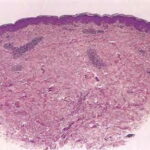

Histopathology. EM is considered the prototype of the vacuolar form of interface dermatitis . The early changes include vacuolization of the basal cell layer; tagging of lymphocytes along the dermal-epidermal junction; and a sparse, superficial, perivascular lymphoid infiltrate . Necrosis of individual keratinocytes in the basal unit occurs, which is the hallmark of EM. Because of its acute nature, there is an orthokeratotic stratum corneum. Mild spongiosis, papillary dermal edema, and extravasation of red blood cells are seen. As the lesion becomes more developed, there is a moderate lichenoid infiltrate of Iymphohistiocytes at the dermal-epidermal junction with exocytosis. More apoptotic keratinocytes within and above the basal epidermal layer are present. The |

intensity of epidermal necrosis varies from vacuolated individual keratinocytes surrounded by lymphocytes (satellite cell necrosis) at the basal unit to confluent necrosis in association with intraepidermal and subepidermal vesicles. The dermal infiltrate comprises lymphocytes and histiocytes. Eosinophils may also be present. Although one study has noted a significant number of eosinophils in drug-induced EM, this has not been noted by others. In the authors’ estimation, a generous number of eosinophils exclude EM. One study has found that an acrosyringium concentration of apoptotic keratinocytes in EM is a clue to a drug etiology . In early lesions of SJSITEN, apoptotic keratinocytes are observed scattered in the basal layer of the epidermis. In established lesions, there are numerous necrotic keratinocytes, even full-thickness epidermal necrosis, and a subepidermal bulla. The dermal inflammatory infiltrate is sparser in TEN than in EM (Fig. 9-278). Extravasated erythrocytes are commonly found within the blister cavity. Melanophages within the papillary dermis occur in late lesions. Eccrine epithelium shows a variety of changes from basal cell apoptosis to necrosis of the duct. |

In general, EM shows less epidermal necrosis, more dermal inflammation, and exocytosis, whereas SJS and TEN reveal more epidermal necrosis, less dermal inflammation, and exocytosis. However, due to the overlapping histologic features among EM, SJS, and TEN, histologic examination-while important for recognizing the spectrum of disorders-is not reliable for classifying the disease. Correlation with clinical presentation is essential. |